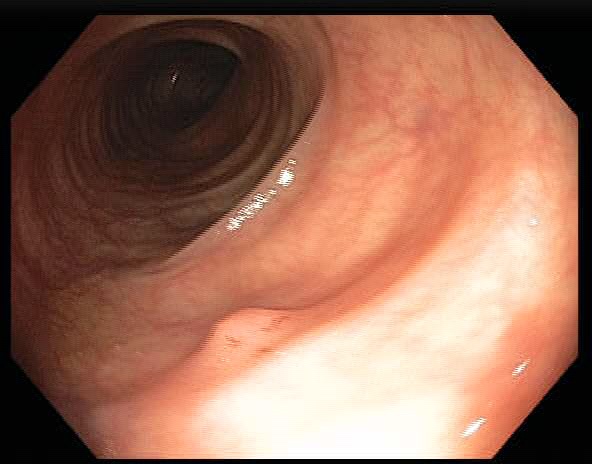

Colonoscopy is the main diagnostic procedure to detect and recognize polyps located on colorectal walls. The accurate detection and correct classification depend on the skills and experience of the endoscopists, however, even for experienced endoscopists, working on conventional colonoscopy for long hours leads to mental and physical fatigue and degraded analysis and diagnosis. Other factors that may affect the classification results include varying illumination conditions, variant texture and appearance, and occlusion. Moreover, different types of polyps are hard to differentiate since they may exhibit a very similar appearance with a subtle difference, as shown in Fig 1. It requires a thorough examination of fine details to distinguish one category form the other. Therefore, an accurate and effective automatic computer-aided system for colonoscopy is required to help endoscopists to detect and classify the type of polyps. This automated recognition mechanism can also be used as a second opinion to determine whether a further biopsy is required for diagnosis, which in turn will greatly reduce the cost of diagnosis. In addition, such an intelligent system can also be used as an educational resource for gastroenterology trainees to reduce the learning curve and cost.

![]() |